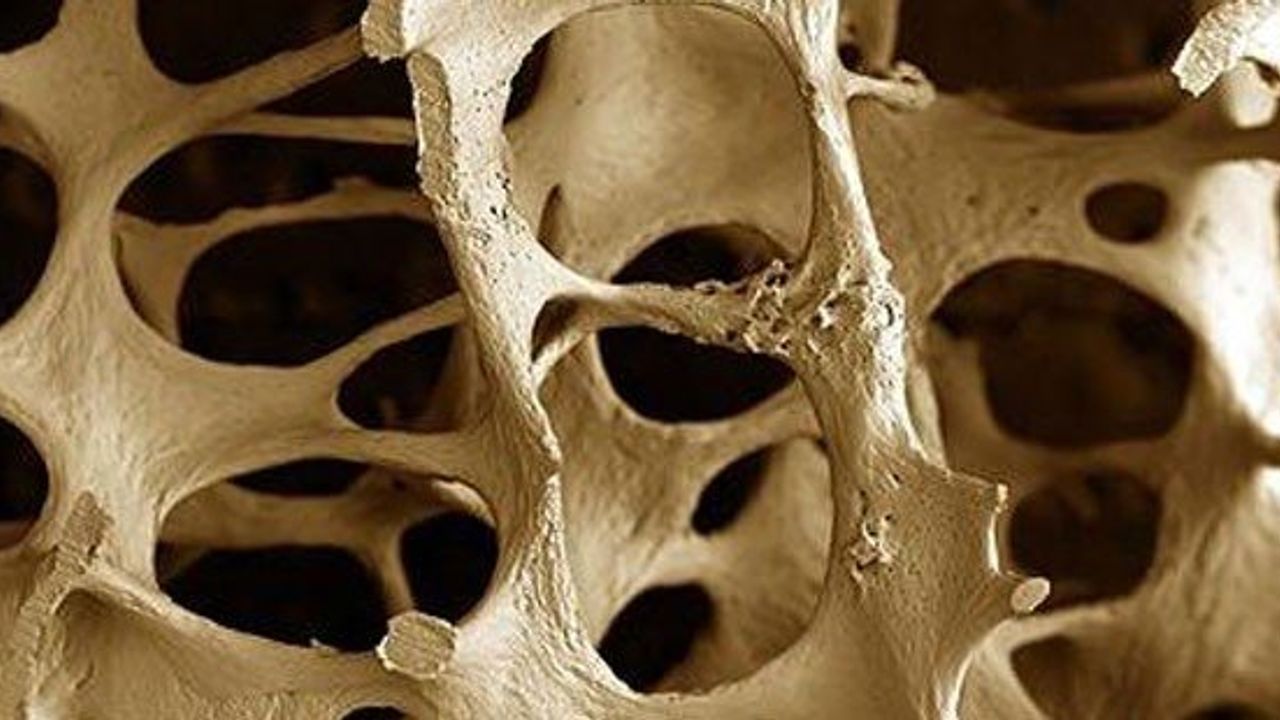

Osteoporoz veya gözenekli kemik, düşük kemik kütlesi ve kemik dokusunun yapısal olarak bozulması, kemik kırılganlığına ve kalça, omurga ve el bileği kırık riskinin artmasına yol açan bir hastalıktır. Kadınların yanı sıra erkekler de önlenebilecek ve tedavi edilebilecek bir hastalık olan osteoporozdan etkilenir. Peki Kemik erimesi (Osteoporoz) neden olur? İşte cevabı.

Osteoporoz tam anlamıyla bir sünger gibi sıkıştırılabilir anormal gözenekli kemiklere yol açar. İskeletin bu bozukluğu kemiği zayıflatır ve kemiklerde sık kırıklara neden olur.

Normal kemik, hepsi de kemiğe gücünü veren protein, kollajen ve kalsiyumdan oluşur. Osteoporozdan etkilenen kemikler, normalde bir kemiğin kırılmasına neden olamayacak kadar nispeten küçük yaralanmayla bile kırılabilir. Osteoporoz ile ilişkili kırıklar hemen hemen iskelet sisteminin her kemiğinde meydana gelmesine rağmen, omurga, kalçalar, kaburgalar ve bilekler osteoporozdan kaynaklanan kemik kırıklarının en fazla görüldüğü alanlardır.